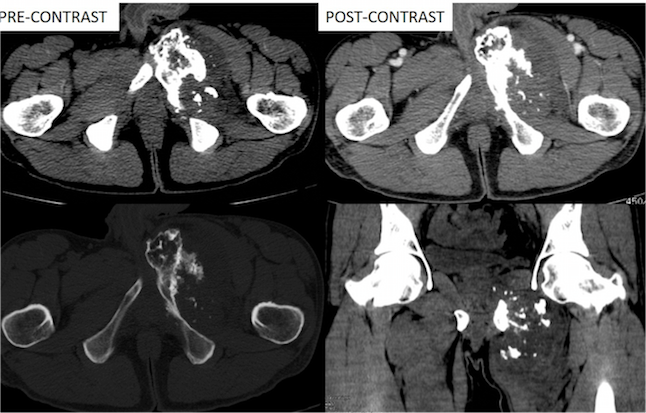

Figure 2. A large lytic expansile mass lesion arising from pubic bone causing underlying cortical expansion and destruction with narrow zone of transition. Central internal ring and arc calcification is also seen.

CT with contrast

A large lytic expansile mass lesion was noted arising from the pubic bone causing underlying cortical expansion and destruction with narrow zone of transition. The lesion shows a central internal ring and arc calcification to suggest chondroid matrix.